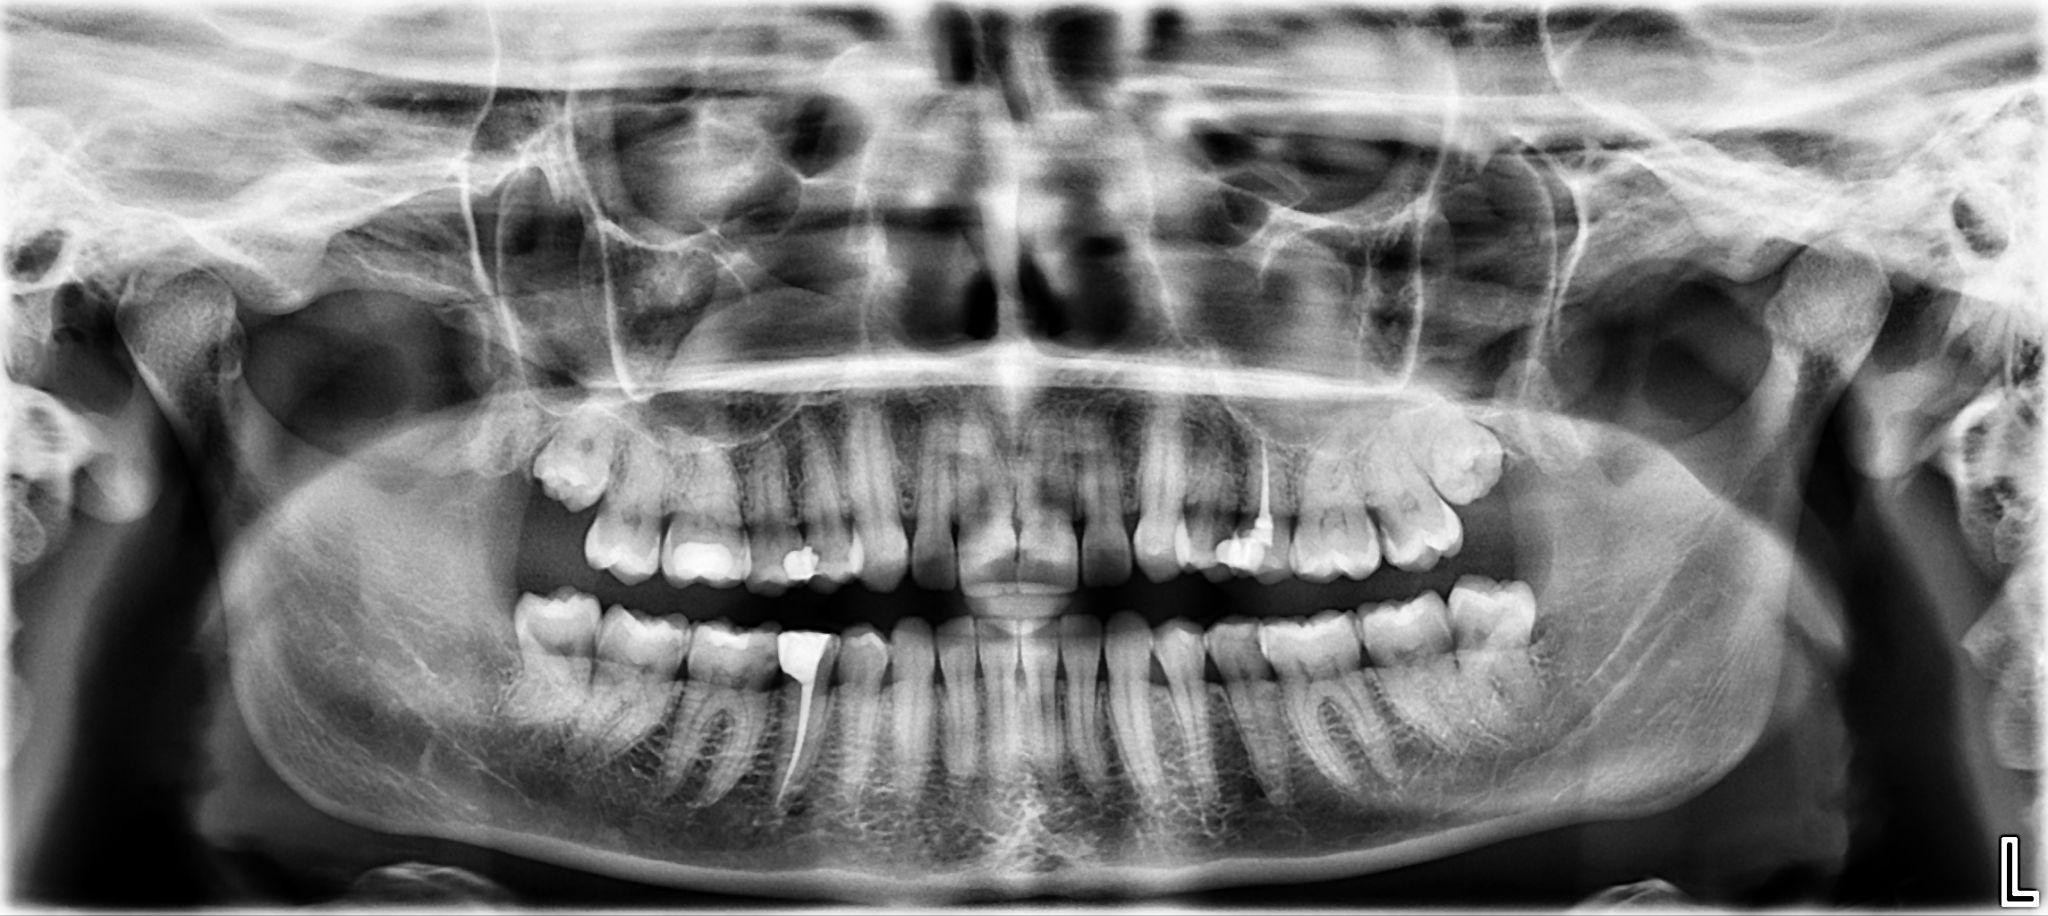

13. What options cannot be selected for the first quadrant of this panoramic X ray?

14. What options cannot be selected for the second quadrant of this panoramic X ray?

15. What options cannot be selected for the third quadrant of this panoramic X ray?

16. What options can be selected for the forth quadrant of this panoramic X ray?

17. What options can be selected for the first quadrant of this panoramic X ray?

18. What options can be selected for the second quadrant of this panoramic X ray?

19. What options can be selected for the third quadrant of this panoramic X ray?

20. What options cannot be selected for the forth quadrant of this panoramic X ray?

21. What options can be selected for the first quadrant of this panoramic X ray?

22. What options cannot be selected for the second quadrant of this panoramic X ray?

23. What options can be selected for the third quadrant of this panoramic X ray?

24. What options can be selected for the forth quadrant of this panoramic X ray?